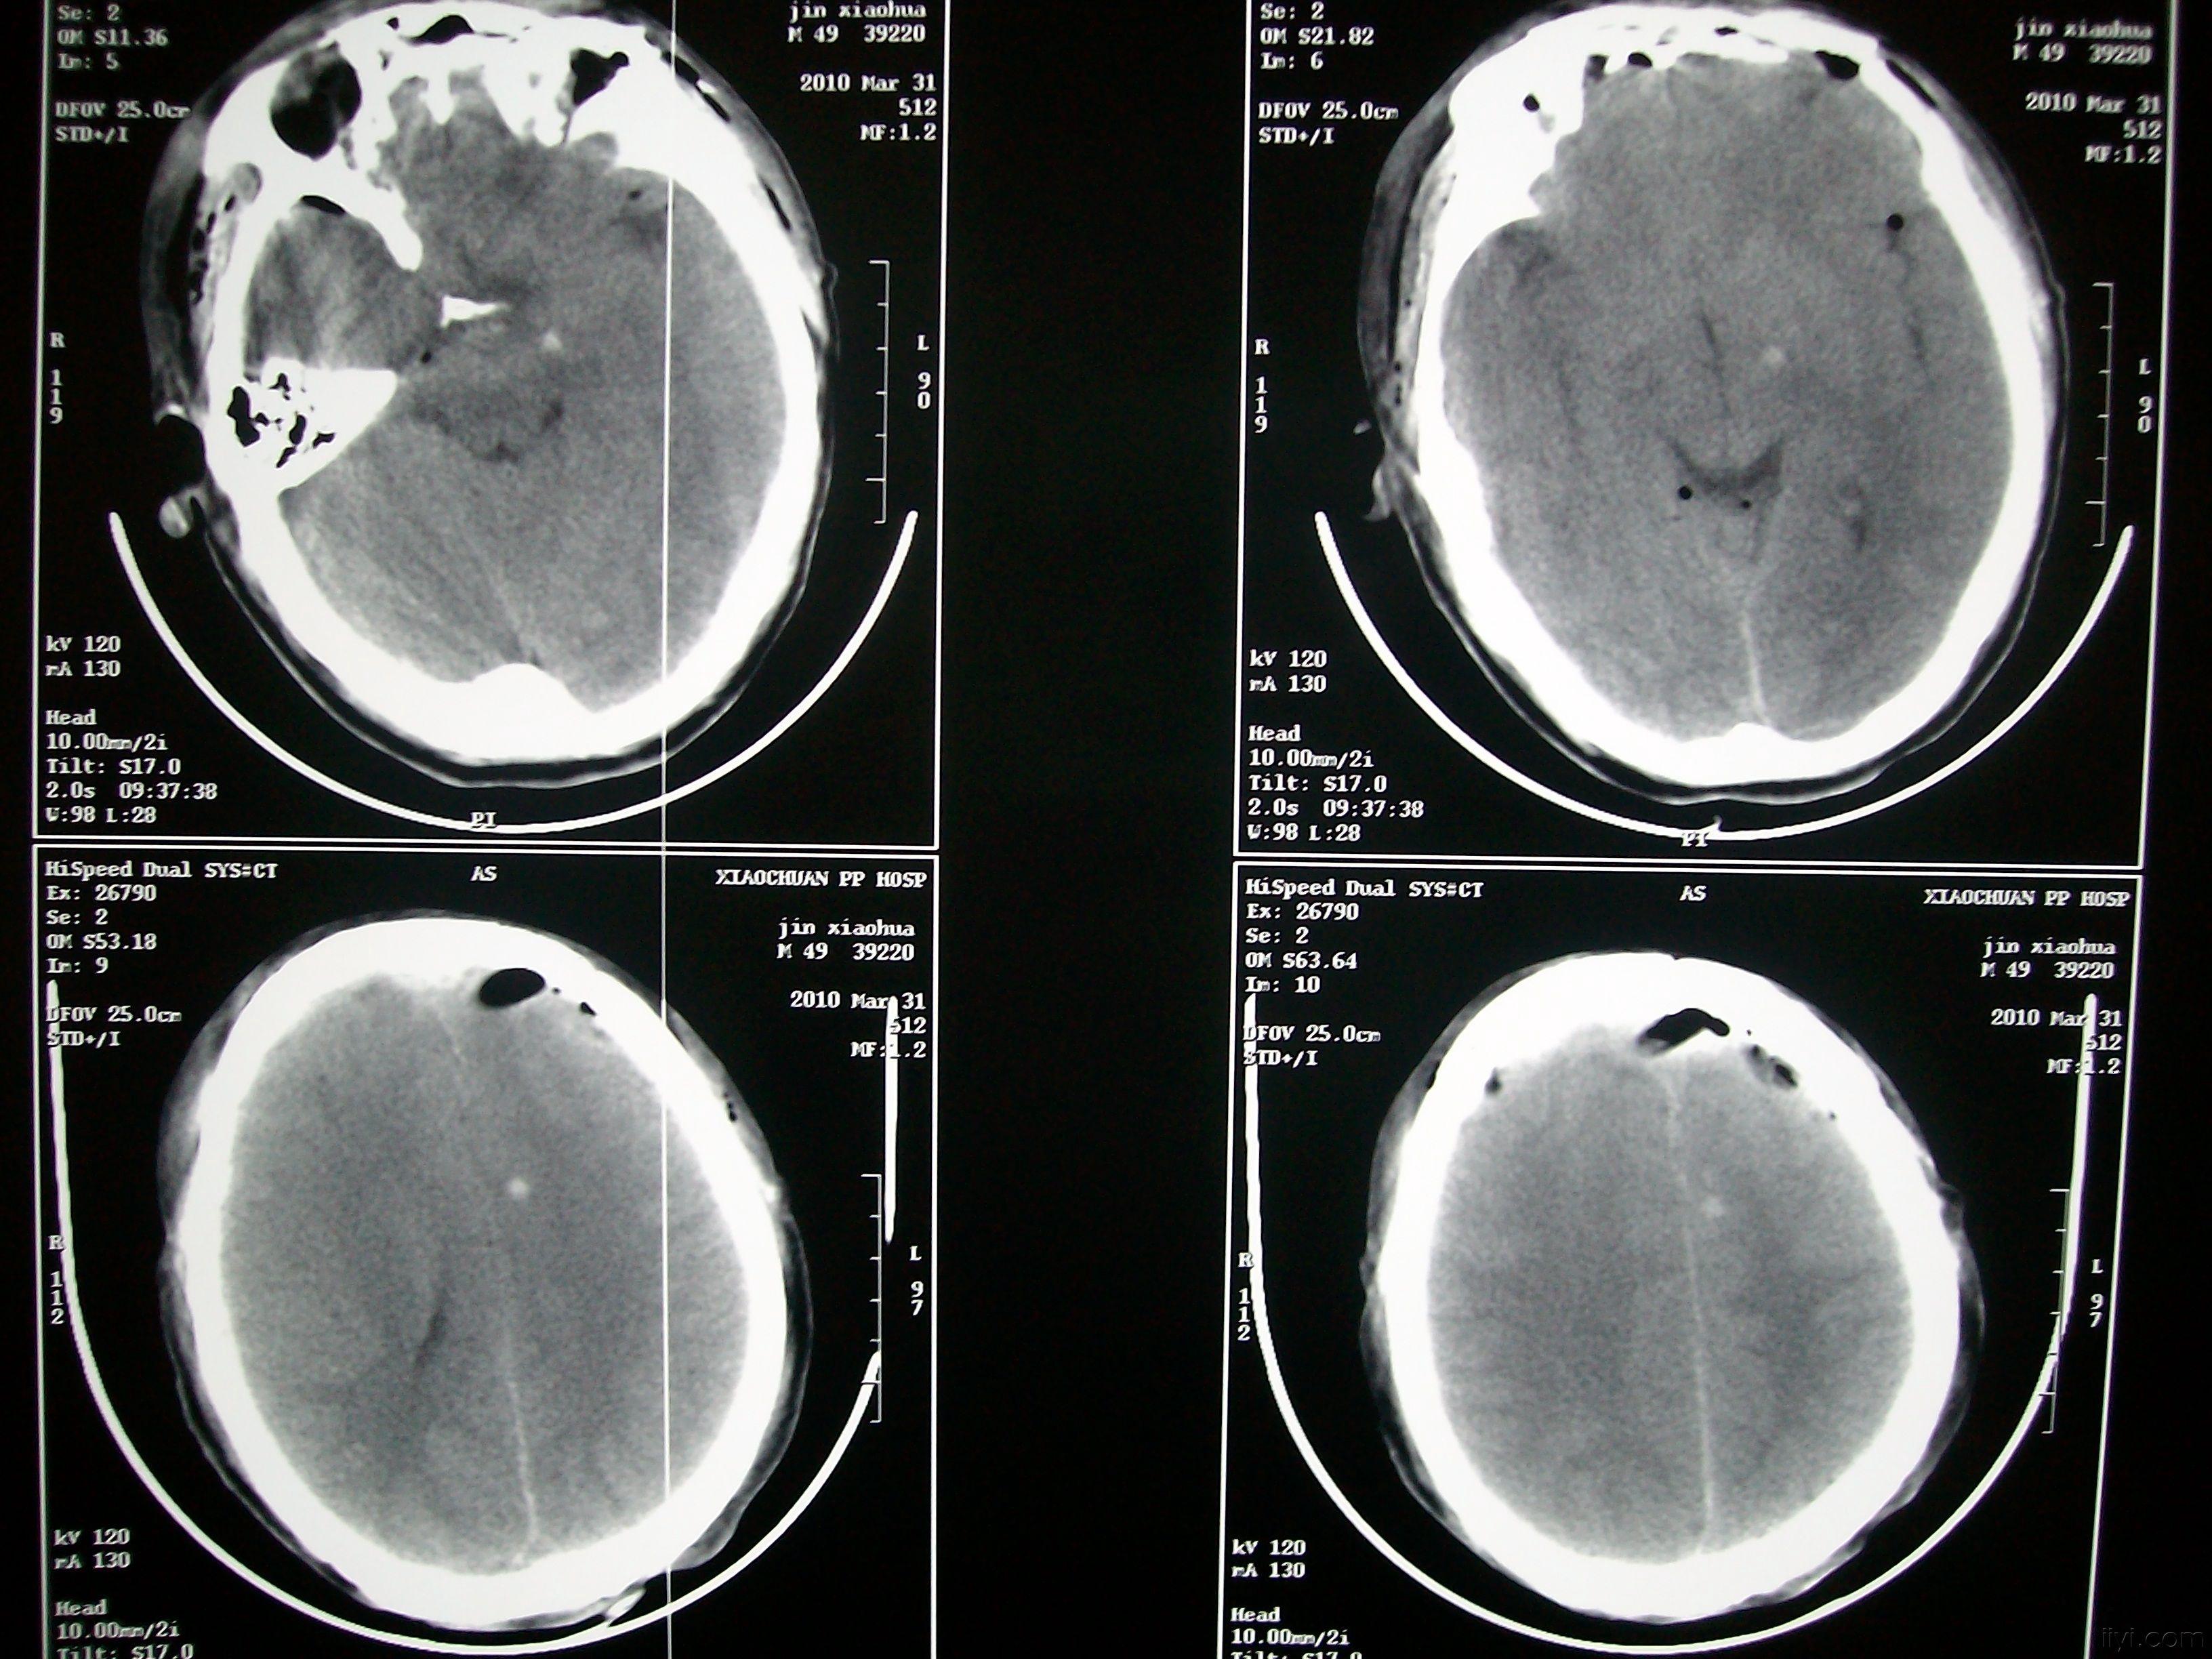

少见气颅一例

脑外伤导致的气颅